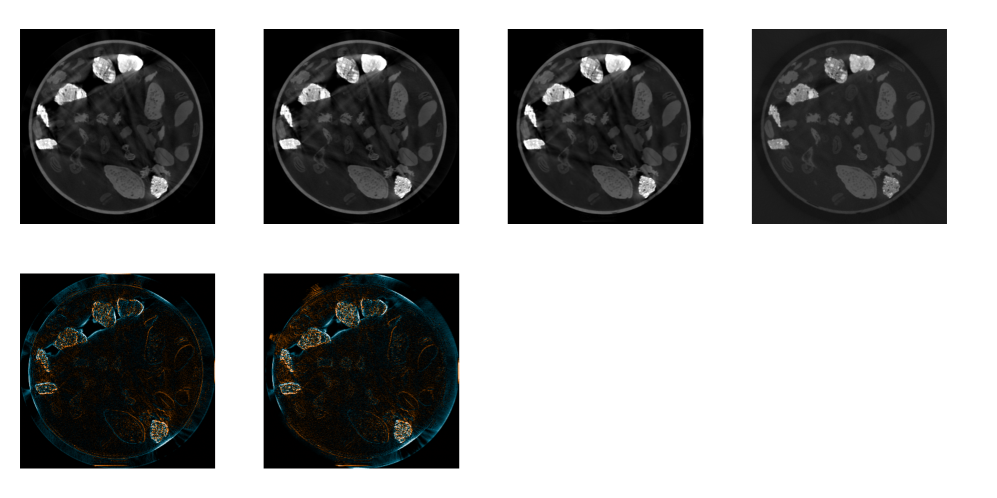

The given image slices from the 2DeteCT dataset using FBP merely pose one possible reconstruction result. Thus, there exists no true ground-truth image information in Experiment B and the quantitative MSE evaluation in the image domain should be omitted. Instead, we can qualitatively compare performance by evaluating FBP reconstructions from high-quality raw data mode (as was used in Experiment A). We indicate this ”ground-truth” image with the abbreviation GT. Figure 9 shows the qualitative comparison in the image domain. Since the images look very similar, difference images to our method highlight their differences. The deviations seem to lie mostly in edges, higher density as well as artifact regions. The orange arrows in Figure 9(b) indicate that some details might get lost in our approach due to smoothing - which was observable in the noise analysis of Experiment A as well. In summary, our method performs subjectively similarly in the image domain while quantitatively outperforming in the projection domain and needing a fraction of the reconstruction time of conventional ML.

Refer to caption(a)FBPMLOursGT*FBP - OursML - Ours0.011cm-0.01\frac{1}{\mathrm{cm}}+0.011cm+0.01\frac{1}{\mathrm{cm}}

Refer to caption(b)FBPMLOursGT*FBP - OursML - Ours0.0061cm-0.006\frac{1}{\mathrm{cm}}+0.0061cm+0.006\frac{1}{\mathrm{cm}}

Figure 9: Reconstructed images for different methods. The ground-truth (GT) image is generated from high-quality acquisition mode projection data without beam-hardening. Difference images are shown w.r.t. our method. The first row images are displayed in level/window=0.05/0.1 1cm\frac{1}{\mathrm{cm}}. The orange rectangle indicates the ROI for Figure (b). First row shown of Figure (b) in level/window=0.05/0.1 1cm\frac{1}{\mathrm{cm}}.